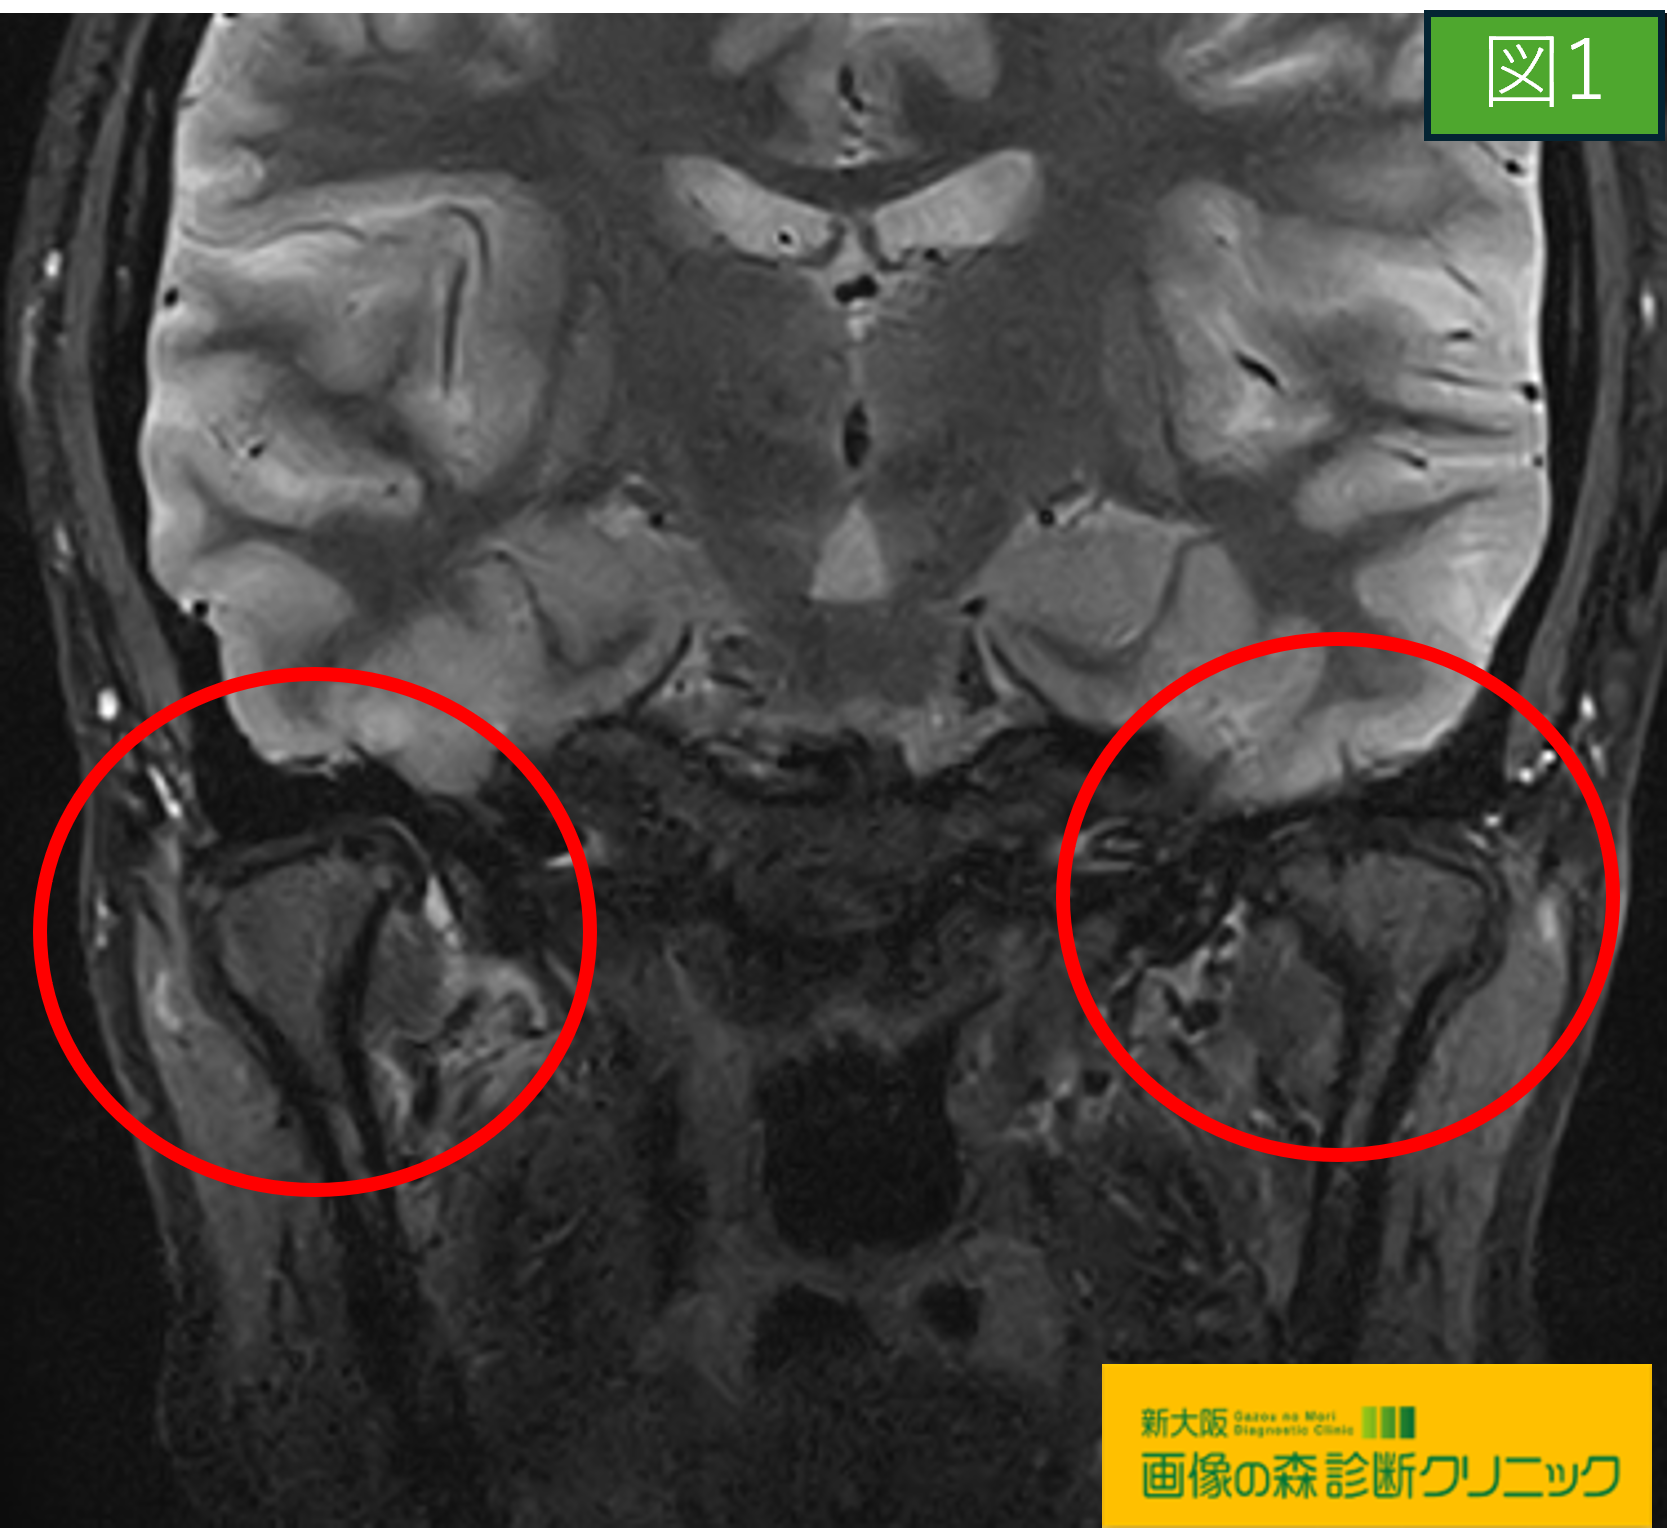

画像から図1・図3は正常顎関節の画像です

〇図1・図2の画像は顎関節部を前から見た画像であり、

それぞれの赤〇内にご注目下さい。

図1の正常画像では、両サイド共に下顎の変形は認めず

大きさも同一であることが分かります。